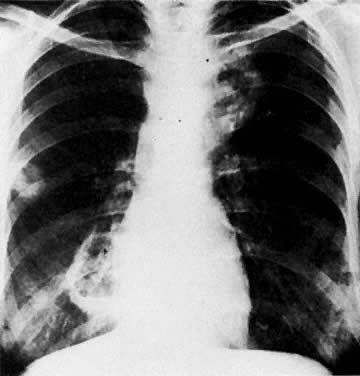

Multiple metastatic nodules in a patient with uterine leiomyosarcoma. Note pleural effusion in the left costophrenic angle.